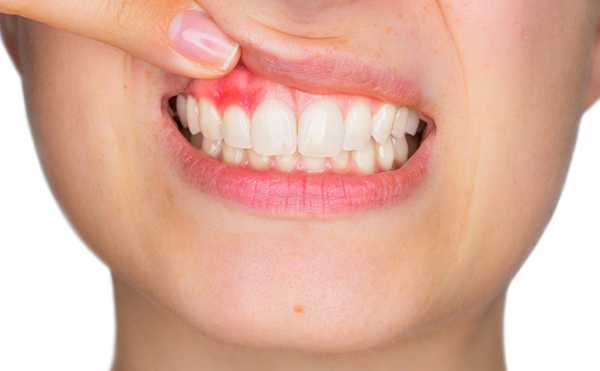

Если больной не начинает лечение и не обращается за квалифицированной помощью, то в результате появляется отечность и покраснение на десне в области гнойного мешка, болевой синдром становится более выраженным и уже не отпускает. Если и в этот период не предпринимается никаких мер, то отечность распространяется на область лица и наблюдается повышение температуры.

Одним из самых болезненных и неприятных стоматологических заболеваний является флюс. Патология характеризуется острым воспалением надкостницы – соединительной ткани, окружающей альвеолярные челюстные отростки, в которых находится зуб. Эта ткань называется периостом, поэтому медицинское название флюса – периостит. Главным симптомом периостита является сильное опухание десны и тканей лица. Припухлость обычно появляется на щеке, но, в зависимости от тяжести и локализации воспаления, в патологический процесс также могут вовлекаться губы, нижние веки и даже боковые крылья носа. На фоне воспаления у больного повышается температура (обычно выше 38°С) и появляются признаки общей интоксикации.

Шишка – характерный симптом флюса.

- покраснения в области десны;

При отсутствии лечения процесс начинает быстро развиваться. Боль становится практически невыносимой и постоянной, появляется отек и покраснение в месте нахождения гнойника, напухает щека, температура поднимается до 38,0-38,5°.